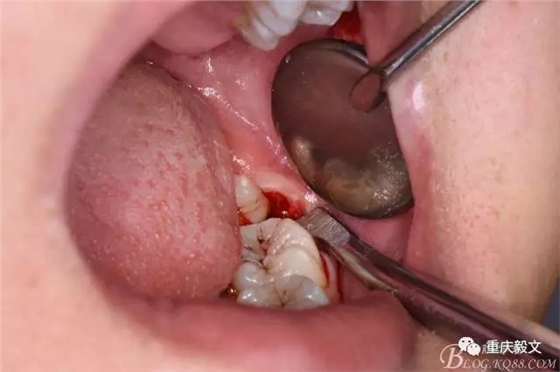

圖6.分離頰側(cè)牙齦,目的使牙冠和牙根能順利從牙齦軟組織脫位。

圖7.高速渦輪鉆分牙

圖8.先從頸部橫斷38

圖9.再把38牙冠近遠(yuǎn)中縱斷